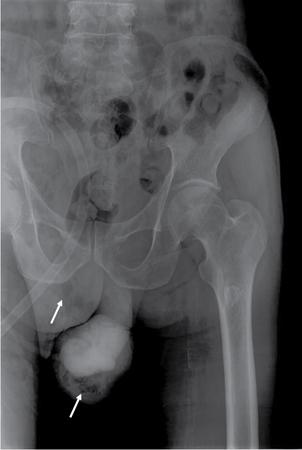

UNDERSTANDING THE ADULT ABDOMINAL RADIOGRAPH: TECHNIQUES AND INTERPRETATION Tanvi Modi Radiography of the abdomen is a common practice for the evaluation of abdominal organs. The anatomy and pathology of digestive, hepatobiliary and genitourinary systems can be assessed using radiographs, either as a stand-alone practice or as a primary imaging modality followed by contrast studies, ultrasound or cross-sectional imaging. In addition, abnormalities of the musculoskeletal or integumentary system can also be deduced on the basis of abdominal radiographs. This chapter intends to give an overview on the techniques and positioning in abdominal radiography as well as interpretation of normal and abnormal features. While superior imaging modalities such as ultrasound, computed tomography (CT), magnetic resonance imaging, capsule endoscopy and the likes have taken over abdominal imaging by and large, radiography still holds a pivotal role in certain situations and conditions, such as: The standard abdominal radiograph is taken in supine position and anteroposterior projection. This is also popularly known as the KUB (kidneys-ureters-bladder) radiograph. Previously, supine as well as erect radiographs were performed in all patients; however, this is not commonly done due to high-radiation dose. For all indications of abdominal radiography, including acute abdomen, supine radiographs are sufficient in terms of radiographic diagnosis, with the exception of perforation for which an erect chest or lateral decubitus radiograph can be performed if there is clinical suspicion. Patient should lie supine on the imaging table with median sagittal plane at right angles to the table and coincident with the midline of the table (Fig. 7.1.1.1). The body is divided into equal right and left halves by the median sagittal which passes through the sagittal suture of the skull. Pelvis should be adjusted so that the anterior superior iliac spines are equidistant from the table top. Gonadal shields, in the case of male patients, should be placed with the upper edge of the shield at the level of pubic symphysis. Although rarely used for female patients, these should be positioned between the anterior superior iliac spines and the pubic symphysis. The centre point of the image receptor should be approximately located at a point 1 cm below the line joining the iliac crests. The X-ray beam should be in a vertical direction, perpendicular to the table top and image receptor at the centre point. Collimation should be such that the soft tissue and subcutaneous region along lateral aspects of the abdominal cavity should be covered within the image. Also, the superior extent involving diaphragm and inferior extent involving the inferior pubic rami is important to look for any lower chest pathologies or any inguinal hernia. 35 × 43 cm (14 × 17 inches) in portrait orientation. On an average, abdominal radiograph exposes a patient to a dose of approximately 1.5 mSv, which is equivalent to 75 chest radiographs or 1/6th dose of a standard CT of the abdomen. The entrance skin dose is approximated to be 4 mGy. At such an effective dose, the additional lifetime risk of fatal cancer is 1 in 30,000. The exposure time is kept short. Patient is asked to exhale completely and hold their breath, with exposure taken at this point of full expiration to ensure imaging of abdominal organs in their natural positions. Modifications of this technique can be made depending on patient habitus and clinical condition. Kilovoltage peak (kVp) should be set to allow adequate visualization of abdominal soft tissue structures as well as semiopaque renal and biliary calculi. Average kVp is set at 70–85 kV. 102 cm (40 inches) Grids are commonly used to reduce scatter radiation. Placement of side marker on the image receptor at the time of radiographic exposure is essential. Bowel pattern depiction should be such that there is minimal lack of sharpness. Standard guidelines for abdominal radiography dictate that the radiograph should extend from the diaphragm up to the level of inferior pubic rami and must include the lateral abdominal wall musculature. The abdomen is divided into four quadrants on the basis of two perpendicular lines (Fig. 7.1.1.7). The vertical line passes through the mid sagittal plane and crosses the umbilicus and symphysis pubis. The horizontal line is a transverse line across the umbilicus at 90 degrees to the vertical line and is situated at the level of L4–L5 intervertebral disc. The quadrants are as follows: Another division system is dividing the abdominopelvic cavity into nine regions using two vertical and two horizontal planes (Fig. 7.1.1.8). The vertical planes, also known as the right and left lateral planes, are parallel to the midsagittal plane between midline and anterosuperior iliac spines on either side. Of the two horizontal planes, the upper transpyloric plane is at the level of lower border of L1 and the lower transtubercular plane is at the level of L5. The nine regions are: On a standard radiograph, the exposure should be such that the stomach, bowel loops, outlines of liver, spleen, kidneys, psoas muscles should be well identified. Also, lumbar transverse processes should be seen. Arch of the pubic symphysis should be visible to evaluate bladder region. A well-centred film without rotation will demonstrate bilaterally symmetrical lower ribs, iliac wings, ischial spines and obturator foramina. Different structures seen on an abdominal radiograph can be classified into five basic densities: Identification of different structures depends on the relative degree of contrast between their densities. The demarcation is clearer in chest and is diminished in abdomen due to relative similar soft tissue density of various structures. On a normal radiograph, relatively large amounts of gas in stomach and colon with minimal small bowel gas can be seen. Further, colonic gas can vary from negligible to extensive, mimicking obstruction pattern; however, usually the gas is enough to delineate colonic haustral pattern. Faecal matter gives a mottled appearance to colonic gas. Short-air fluid levels on an erect radiograph may be seen even in normal cases. The normal appearance of small bowel loops on an abdominal radiograph follows the rule of threes: Stomach is seen in the left upper quadrant and is visualized when distended with air. It is commonly seen extending from T11 to L2 level. Common feature identifying the stomach is the fundal gas which is usually seen as an air fluid level within the gastric lumen. Small bowel loops are distributed to the centre of the abdominal cavity and large bowel loops are peripheral. Duodenum is predominantly situated in right upper quadrant. It extends to left upper quadrant in the region of duodenojejunal flexure. Jejunum occupies the left upper and lower quadrants and is easily identified due to the presence of thick, numerous, closely spaced valvulae conniventes (Fig. 7.1.1.9A). The ileum occupies both lower quadrants and extends into right upper quadrant. Ileum has few and less prominent valvulae as compared to jejunum (Fig. 7.1.1.9B). Ascending and descending colon are retroperitoneal and have relatively fixed positions along lateral aspect of the abdominal cavity on either side. Transverse and sigmoid colon, on the other hand, may have a variable position due to their mobility along mesocolon and redundant pattern. These can be identified with confidence on account of haustrations and faecal matter (Fig. 7.1.1.10). Haustrations are usually well seen in ascending and transverse colon and poorly delineated beyond splenic flexure. Caecum is in the right lower quadrant, though it may be mobile or pulled up. Rectal gas is usually seen in the midline at the level of pelvis and its presence rules out large bowel obstruction. All these positions may vary due to anatomical conditions such as malrotation or pathological conditions, for example volvulus. Liver, spleen and renal outlines cannot be completely traced with precision due to the overlap by bowel loops. On a frontal projection, the liver appears as a triangular structure occupying right and left hypochondrium and epigastric region. Occasionally, the right lobe may be seen extending lower than the right renal shadow. This is a normal variant known as Reidel’s lobe. Gall bladder is situated in the posterior and inferior region of the liver and any pathology of the gall bladder should be looked for in this region. On a lateral radiograph, the gall bladder is anterior to the midcoronal plane. This helps in distinguishing gall bladder calculi from renal calculi, which will be more posteriorly situated. Spleen is seen in left upper quadrant/left hypochondrium, flushed to left lower ribs and left hemidiaphragm. Pancreas is present in the epigastric region (right and left upper quadrants) and is usually not identified in the absence of a pathology. The kidneys are bean-shaped retroperitoneal organs which are seen on either side of the vertebral column and lateral to psoas muscles. Due to the presence of liver on the right side, this kidney is slightly lower in position as compared to its contralateral counterpart. The visualization of kidneys on radiographs is facilitated by the surrounding fatty capsule. Kidneys lie between T11–12 and L2 level, with left kidney 1 cm higher than the right. Psoas muscle shadow can be normally seen along lateral aspect of lumbar spine bilaterally and is mildly concave (Fig. 7.1.1.11). Abdominal wall muscles are not routinely assessed on radiography; however, inclusion of lateral abdominal wall (muscles as well as subcutaneous plane) is a must while performing radiography. The flank stripe or the properitoneal fat stripe is a fat density linear concavity seen along lateral abdominal wall (Fig. 7.1.1.11). It is bound by the paracolic gutters and air-filled ascending and descending colon. All the solid organs in the abdomen are identified due to the fat density outlining them. Distortion of these fat lines helps in identifying organomegaly or focal mass lesions. The dome of urinary bladder is outlined by fat, which aids in differentiating its density from other soft tissue structures of the pelvis. Not all calcifications seen on abdominal radiograph are abnormal. Some may depict age-related changes such as vascular calcifications involving abdominal aorta, pelvic vessels, splenic artery in the region of left upper quadrant. Within the pelvis, phleboliths may be seen and mistaken for urinary calculi. Assessment of lumbosacral spine, iliac bones and femoral heads can be made on the basis of plain radiography. Degenerative changes may be commonly seen. Lower ribs can also be evaluated for pathologies. Dilated small bowel loops with rounded soft tissue density in midline over umbilical region suggests obstruction secondary to umbilical hernia. Pneumoperitoneum must be looked for in all cases of acute abdomen. While erect chest and left lateral decubitus radiographs can detect even 1 mL of free air, there are multiple signs on supine radiograph to suggest this diagnosis, for example Rigler’s sign, falciform ligament sign, football sign (Figs. 7.1.1.24 and 7.1.1.25). Retroperitoneal perforation may demonstrate air outlining psoas muscles and retroperitoneal organs. Small amount of free air may persist in the abdominal cavity up to 3 weeks after surgery, although it usually resolves within a week. Clinical history is important in such cases. Air foci within the bowel wall may represent bowel ischaemia/strangulation. Linear gas patterns in right hypochondrium may be due to two causes, that is pneumobilia and pneumoporta. The former can be seen normally postbiliary surgery, sphincterotomy, ERCP or in the case of abnormal fistulous communication between bowel and biliary tree (Fig. 7.1.1.26A). Pneumoporta (Fig. 7.1.1.26B) is a red flag and warrants further investigation to look for conditions such as mesenteric ischaemia and toxic megacolon. Pneumobilia is more centrally located whereas air shadows in pneumoporta are seen reaching up to periphery of liver. Air foci over renal shadows (Fig. 7.1.1.27), gall bladder or pancreas, in the absence of recent procedural history, suggest fulminant infection and mandate urgent intervention. Central midline calcific foci between T9 and T12 vertebrae can be attributed to calcific pancreatitis (Fig. 7.1.1.28). In the left upper quadrant, areas of calcification seen involving a shrunken spleen may be seen in autosplenectomy. In right upper quadrant, calcified gall stones may be seen. These tend to be small, multiple, uniformly circumscribed and ring-like in appearance with central translucency (Fig. 7.1.1.29A). Mercedes Benz sign, a triradiate pattern of gas lucency, is associated with gallstones. In contrast, renal calculi are more commonly solitary, irregular, of homogenous density, conform to renal calyceal or pelvic outline (Fig. 7.1.1.29B) and are sometimes of staghorn configuration. On lateral view, the gall stones are more anteriorly located as compared to renal calculi, which may be partly superimposed on lumbar vertebrae. Ureteric calculi tend to overlap bony structures such as lumbar transverse processes (Fig. 7.1.1.29B) or sacroiliac joints. Extensive or patchy, curvilinear calcification of gall bladder wall is known as porcelain gall bladder which is often associated with malignant transformation. Calcification involving adrenal glands may be secondary to infection or haematoma, or a congenital condition known as Wolman’s disease where there is bilateral involvement. Discontinuous discrete midline tram track calcification in the abdomen may indicate atherosclerotic changes in abdominal aorta and branch vessels. However, when the calcification is in a globular pattern and seen below the level of L2 vertebra, aortic aneurysm should be suspected (Fig. 7.1.1.30). Appendicoliths, though not commonly seen, may sometimes be detected in right iliac region. Pelvic calcifications: vesical calculi, distal ureteric or vesicoureteric junction calculi, calcified fibroids, ovarian dermoid with tooth-like calcifications (Fig. 7.1.1.31) may be the cause of abdominal pain and should be diligently looked for. Vesical calculi are usually more large and central in location whereas calcification due to fibroids may be more lateral. Schistosomiasis is another cause of bladder wall calcification, as is calcification of bladder tumours. Phleboliths tend to be bilaterally symmetrical, with a lucent centre unlike ureteric calculi. While it is believed that phleboliths are located below the level of ischial spines and ureteric calculi above, this is not always true and should be confirmed with CT. Fluid may collect adjacent to properitoneal fat line, forming a linear soft tissue density separating the fat line from the ascending or descending colon. Hellmer’s sign demonstrates medial displacement of lateral edge of liver (hepatic angle), due to fluid collection or ascites. Gross ascites may appear as generalized abdominal haziness or diffuse increased density of pelvis. Abscesses can involve any solid organ and in such cases may be difficult to demonstrate on plain radiography alone. Enlargement of organ or faint gas densities within can be suggestive of the same. In the case of peritoneal abscess, mottled density due to air, fluid and necrotic contents point towards this diagnosis, especially in right iliac fossa in association with appendicitis. Retroperitoneal abscess, similar to any retroperitoneal mass, may cause displacement of retroperitoneal structures (Fig. 7.1.1.32). Subdiaphragmatic abscesses may show concomitant ipsilateral pleural effusion (Fig. 7.1.1.33). These should be differentiated from Chilaiditi syndrome. Fluid and soft tissue lesions present with the same density on radiographs. While it is difficult to characterize the lesion and organ of origin, clues for the same can be provided by organomegaly (Fig. 7.1.1.34), distortion of fat surrounding solid organs, displacement of bowel loops or solid organs. For example, a retroperitoneal lesion may cause anterior or inferior displacement of kidney, a pelvic mass may cause upward displacement of small bowel loops. Different densities such as fat or calcification may help in identifying organ of origin (e.g. fat and tooth densities seen in ovarian dermoid). Convexity of margins of psoas muscle on an abdominal radiograph can be due to haematoma, abscess or intramuscular tumour. Radiographs are performed for the initial diagnosis of foreign body in the abdomen including type, number of foreign bodies, location, size and shape (Fig. 7.1.1.35). Radiolucent foreign bodies such as wood, plastic, chicken bones will not be easily identified on radiography. Low kVp (65–70 kVp) can increase contrast and help identify these objects. In addition to an abdominal radiograph, chest radiography is also performed to exclude aspiration or oesophageal location of foreign body. Ingested or introduced foreign bodies may cause complications such as obstruction, perforation, fistula formation and sepsis. Hence, once their presence is confirmed, follow up radiography must be performed until they are eliminated. One must look for fractures/dislocation injuries involving the vertebrae or pelvic bones, especially after history of trauma. Lucent expansile lesions or sclerotic bony deposits which represent neoplasms, absent pedicle sign in cases of metastasis, metabolic bony changes such as rugger jersey appearance, Paget’s disease, arthropathies such as ankylosing spondylitis with bamboo spine appearance and sacroiliitis (Fig. 7.1.1.36) are some of the conditions which may be diagnosed based on an abdominal radiograph. Overlap of bowel loops over iliac blades may lead to a misdiagnosis of lucent lesions and should be evaluated with caution. Basal pneumonia may be the cause of acute abdominal pain and should be looked for in abdominal radiography. Similarly, pleural effusion, pericardial effusion, calcified pleural plaques, achalasia, interstitial fibrosis are few other findings that can be seen in lower chest on an abdominal radiograph. Basilar atelectasis can give a deceptive appearance of pneumoperitoneum (Fig. 7.1.1.37). Surgical clips, commonly in right hypochondrium after cholecystectomy, drainage tubes, ventriculoperitoneal shunts, femoral line catheters, IVC filters, stents (vascular, renal, biliary) (Fig. 7.1.1.38), stoma bags, contraceptive devices are some structures that may be seen in an abdominal radiograph. Correct knowledge of patient history and normal locations of these structures prevents misdiagnosis. Certain artefacts may be projected upon the radiograph due to surface structures such as trouser buttons, body piercing, sequins over clothing and should not be considered as a pathology. Multiple skin surface nodules in cases of neurofibromatosis, soft tissue focal swellings, such as abscesses, lipomas, haematomas, desmoid tumours and malignant lesions may be incidentally seen on radiography. These can be further evaluated using ultrasound or CT. Subcutaneous emphysema is another finding that may be seen in lower abdominal wall secondary to retroperitoneal perforation or diffusely along abdominal wall in the case of bowel perforation (Fig. 7.1.1.39). Foreign bodies such as bullets and pins may be seen lodged in abdominal wall. A systematic approach to abdominal radiographs is important for accurate diagnosis as follows: Despite the development of newer techniques for imaging of the abdomen, plain radiography still holds an important place in the initial assessment of acute abdomen. Positive and negative findings on an abdominal radiograph can direct further investigation. Ideal positioning, recognition of normal appearances and keen scrutiny for pathologies is a sine qua non for radiologists reading a plain film of the abdomen. OESOPHAGOGRAM Padma V. Badhe, Vikram Reddy, Sultan Moinuddin Shaukatali, Zillani Alam, Ravi Varma, Abhishek Bairy, Dasari Ravikiran, Revati Tekwani, Soniya Patankar, Megha Nair, Gautham Shankar Oesophagogram is the process of obtaining radiological images and simultaneous motion recording to evaluate function and disorders of pharynx, oesophagus and proximal stomach. Oesophagogram is usually done primarily to evaluate dysphagia. Some of the common indications are oesophageal motility disorders, strictures, gastro-oesophageal reflux disease (GERD) and suspected masses. It can also be used to detect uncommon anomalies like vascular rings/slings and aberrant anatomy. It also helps to evaluate further in cases where there is inability to pass upper GI scope. Double-contrast oesophagogram is mainly indicated in early mucosal disease like erosion, polyp, infection and tumours. If a motility disorder is suspected, dynamic technique (e.g. videofluoroscopy) is used for dysphagia or aspirations in cases of stroke, neuromuscular disorders, post head and neck surgery or radiation. Barium oesophagogram is contraindicated in suspected cases of perforation and tracheoesophageal fistula, aspiration, rarely if there is hypersensitivity to barium suspensions. It is also contraindicated in suspected oesophageal perforation where a water-soluble contrast agent is more suitable. However, ionic water-soluble contrast agent is better avoided in cases of aspiration or fistula with airway. The contrast examination of the pharynx is dangerous in cases of acute epiglottitis and must be ruled out on plain radiograph. An 80% w/v barium suspension is used in full column views. However, 200%–250% w/v barium suspensions is usually required for mucosal relief films. The barium sulphate mixture is fed to the patient either by spoon, by glass, or through a drinking straw, depending on its consistency. In videofluoroscopy, the pharyngeal phase of swallowing is usually safer with barium pudding than with thick barium and safer with thick barium than with thin barium. However, if the major abnormality is poor pharyngeal contraction leading to stasis in the piriform sinus (and epiglottic tilt is normal), a thin liquid is safer. Epiglottic motility is better assessed with thin barium because thick barium often obscures the epiglottic tip. Fluoroscopic equipment capable of cine fluoroscopy and capability for rapid sequence spot images (high frame rate) is needed for this examination, Barium suspension, straw, glass, Lead apron and radiation protective equipment. The patients are instructed to fast after midnight before the day of the examination. The pharynx should be made as dry as possible during the examination as high-density barium adheres to dry pharyngeal mucosa. Activities like smoking, chewing gum and lozenges must be abstained before the procedure as they impair barium coating by increasing the salivary secretion. Regular oral medications must be taken with sips of water; however, insulin must be skipped on the morning of examination. The major principles of a good oesophagogram includes mucosal coating, distension and projection. A routine oesophagogram consists of screening of the oral, pharyngeal and oesophageal phases of swallowing, single and double-contrast examination of pharynx, single contrast, double-contrast and mucosal relief views of the oesophagus. In cases of dysphagia, the examination is tailored depending on whether the symptoms are either pharyngeal or oesophageal and initial fluoroscopic findings. If patients’ symptoms are suggestive of oral or pharyngeal disorder then pharynx is evaluated first. Similarly, if patient is suspected to have thoracic oesophageal disease then, double-contrast examination of the oesophagus is performed before the pharyngeal evaluation. During an oesophagogram the positioning of the patient varies according to the type of examination (Table 7.1.2.1).